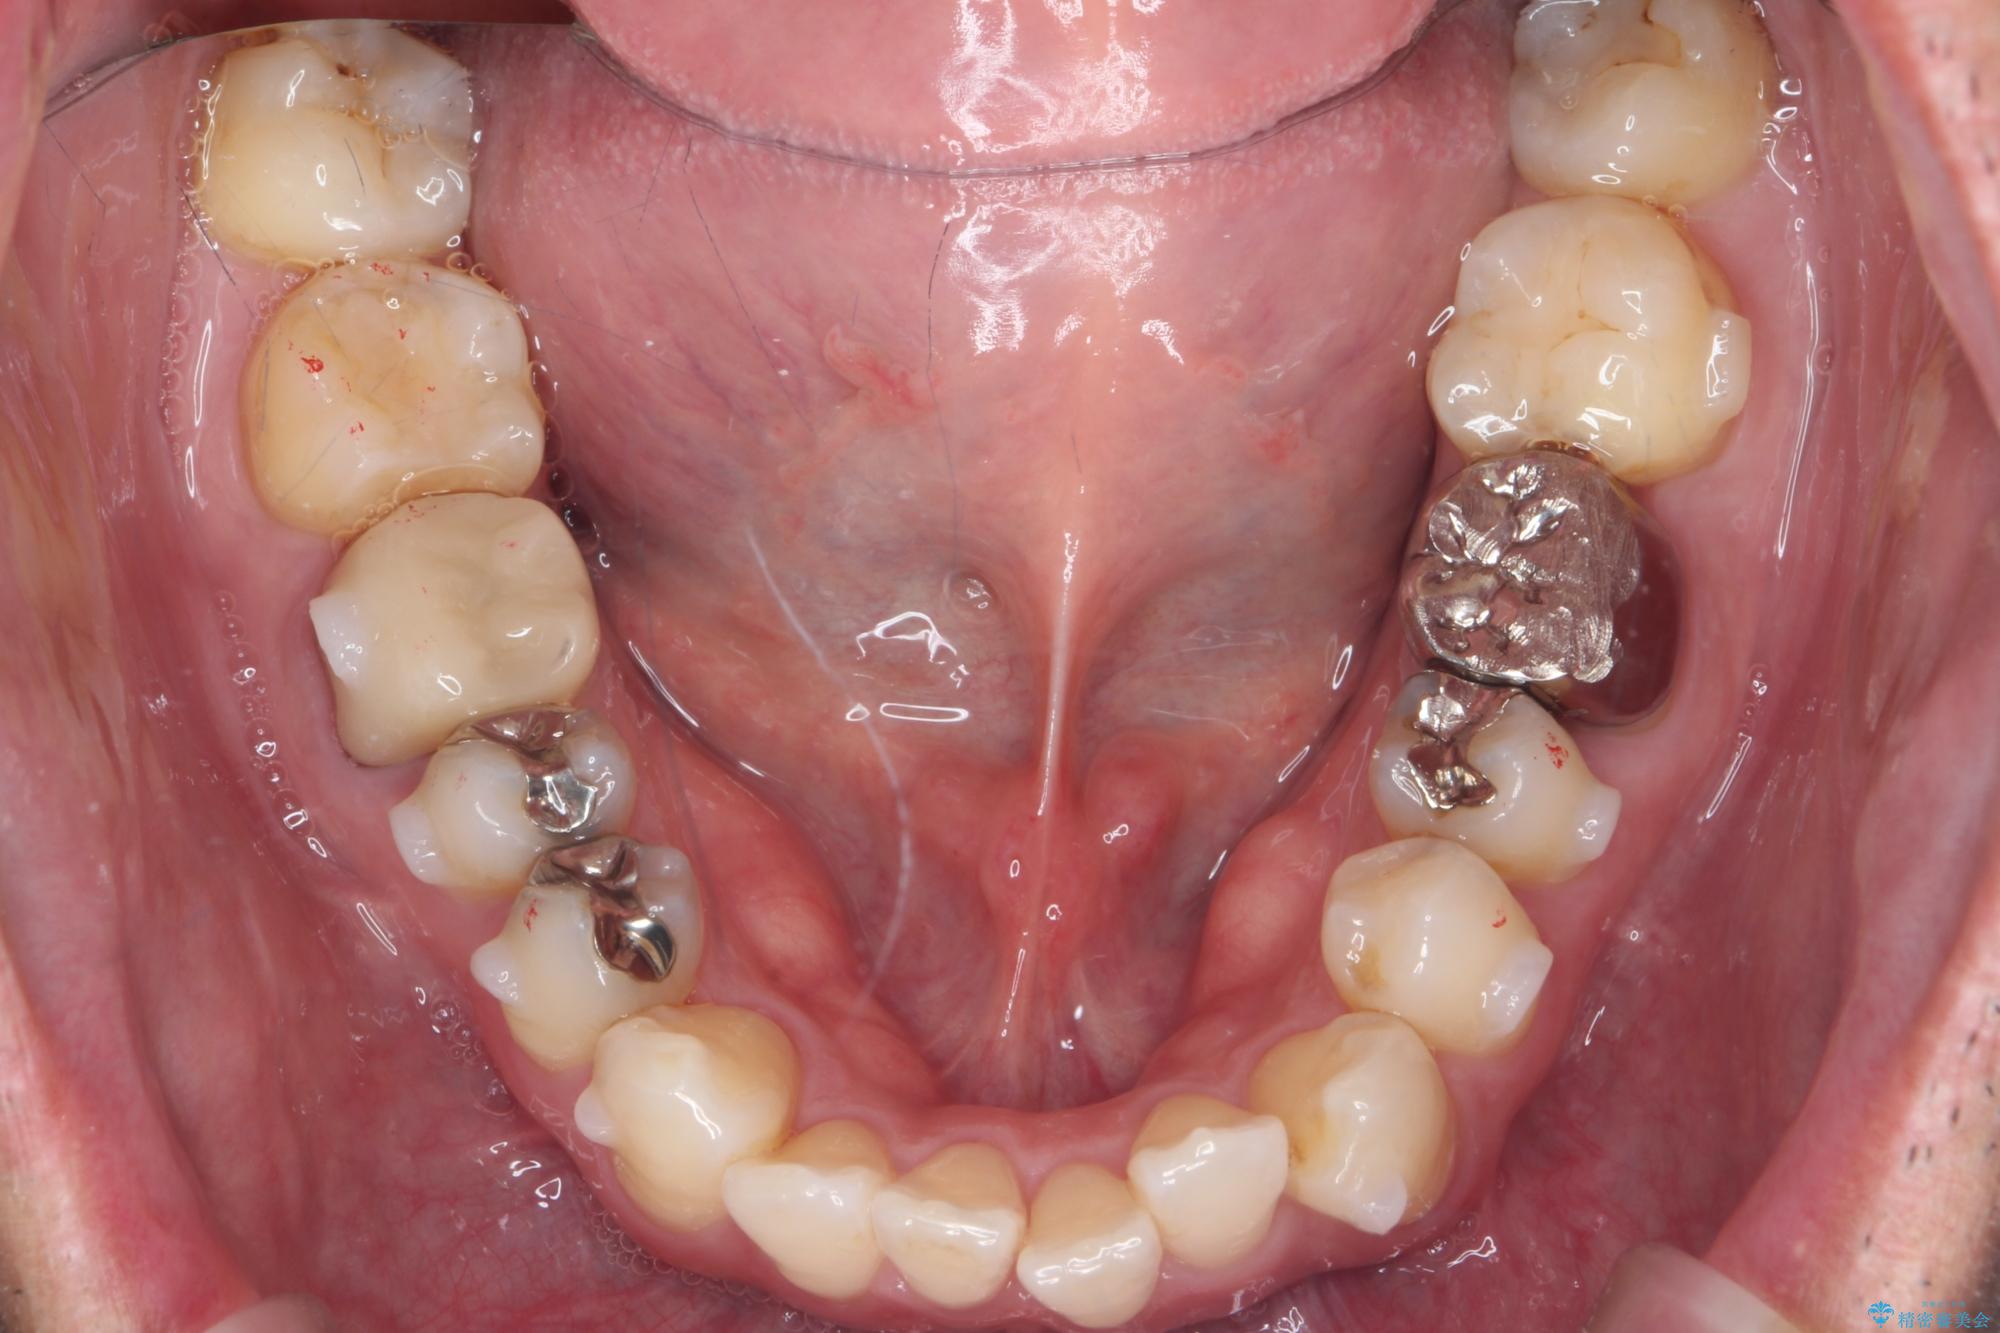

矯正と虫歯のセラミック治療 総合歯科治療の実践

- 突き出た前歯の角度の改善と虫歯治療の改善を求めて来院されました。

虫歯を除去したのち、マウスピース矯正治療を行い、歯並びやがたつきを改善したのち、セラミックに置き換えることで審美性の向上を計画します。

矯正や虫歯治療、セラミック治療といった複合的な治療を一医院で行うことができるのが当法人の大きな特長です。